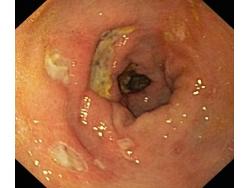

Wrzód trawienny